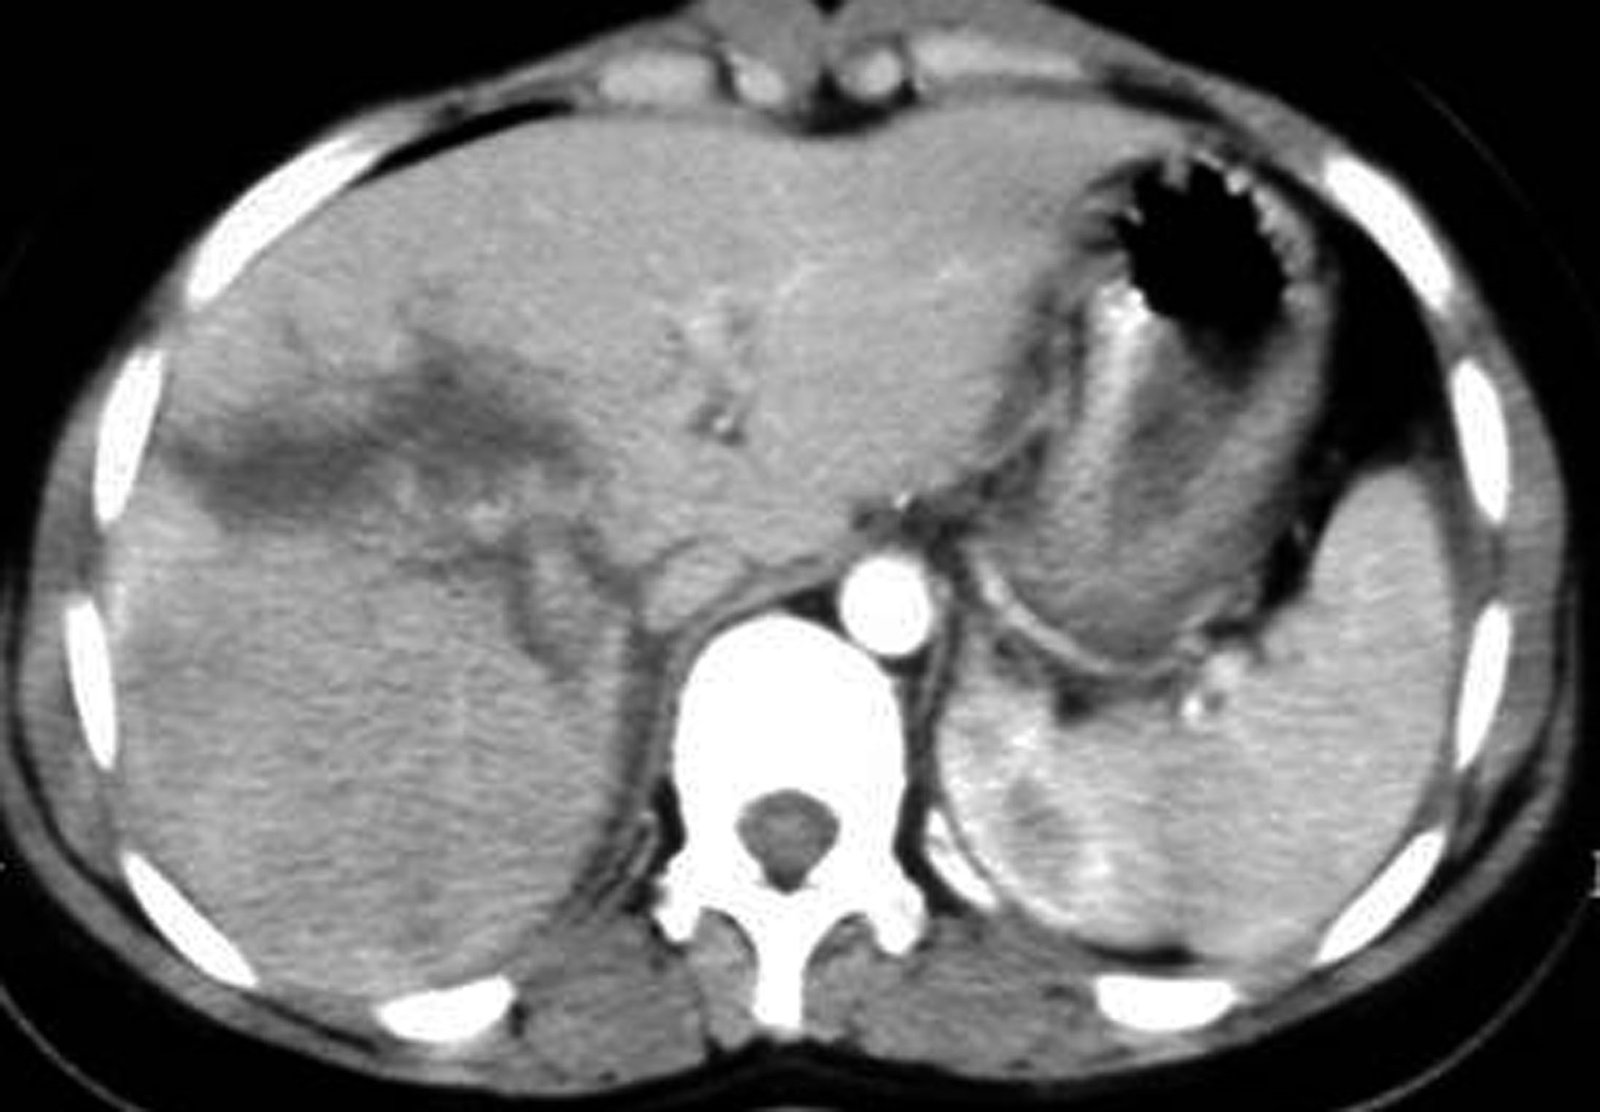

Qarın müayinəsi

İkinci yoxlamanın qarın müayinəsində ilk hədəf qarındaxili qanaxma və orqan zədələnməsinin olub-olmadığını aşkarlamaqdır, zədələnmənin xarakteri isə adətən laparotomiya/laparoskopiya və ya bəzən KT ilə dəqiqləşdirilir. Qarındaxili zədələnməni yoxlamaq üçün zədələnmənin açıq yoxsa qapalı olmasından asılı olaraq yanaşma seçilir. Açıq yaralanmalarda yara təftişi, qapalı yaralanmalarda görüntüləmə müayinələri (USM, KT) ilk planda tutulur. Aşağıdakılardan hər hansı biri varsa qarındaxili zədələnməni göstərir:

- Görüntüləmədə qarında maye, ekstravazasiya, hematoma və s.